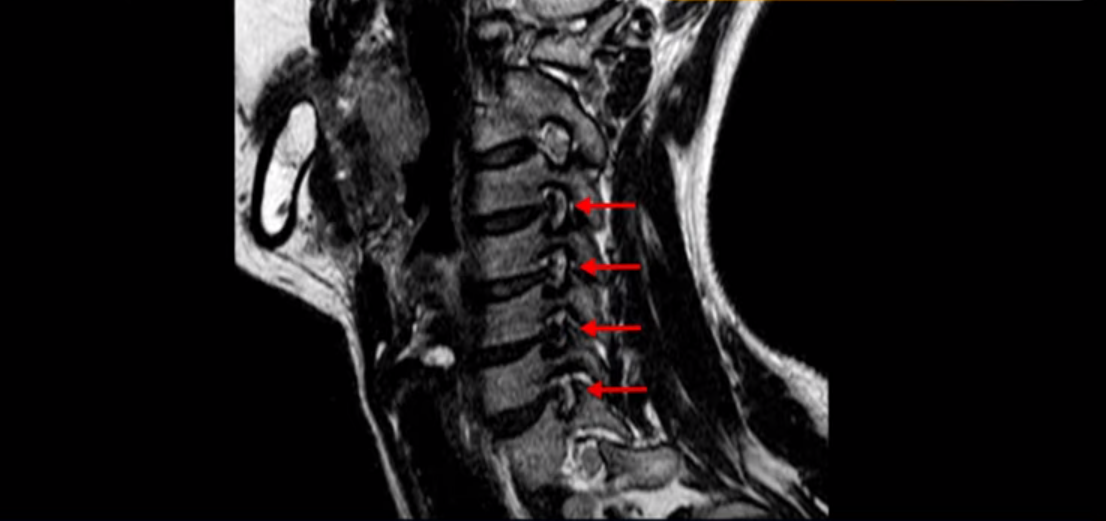

우선 이분 MRI를 보기 전에 이분 증상에 대해 말씀 드리면 오른쪽 팔저림과 방사통 및 어깨 통증이 있습니다. MRI를 보면 4번 5번에 디스크 파열이 보입니다.

밀려나온 디스크가 위로 타고 올라가 있는데 보시다시피 가운데로 밀려 나와 있습니다.

그래서 이게 오른쪽 통증의 원인일 수도 있고 아닐 수도 있습니다. 5번 6번은 왼쪽으로 밀려 나와있으니까 오른쪽 통증의 원인이 아닙니다.

그런데 이분 목을 보시면 여러 마디의 뼈가 퇴행이 진행되어 있습니다. 뼈가 깍두기처럼 각지고 예뻐야 하는데 끝이 조금씩 변형되어 뾰족하게 자라고 있습니다.

이런 게 협착을 일으킵니다. 그래서 우선 오른쪽 신경구멍 즉 추간공을 살펴보면 맨 위의 한마디를 빼고는 다 좁아져 있습니다.

특히 5번 6번 구멍이 가장 좁습니다. 이걸 협착이라고 합니다.

사실 여러 신경 구멍이 다 좁아져 있기 때문에 정확히 어느 마디가 방사통을 일으키는지 정확히 알기 어렵습니다. 그래서 만일 수술을 한다면 정확히 어느 마디가 진짜 원인인지 파악하지 못한 채 한다면 수술이 크게 실패할 수도 있습니다. 또한 이분처럼 여러 마디가 안 좋아서 수술한 마디의 위나 아래가 상태가 좋지 않으면 유합술 후 그 위나 아래에서 또다시 문제가 생기는 인접 분절 질환이 수술 후에 발생할 수도 있습니다. 이런 정도는 알아두는 게 좋습니다.